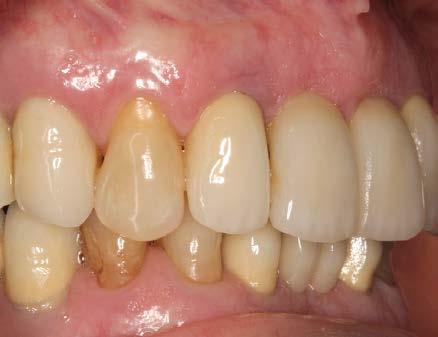

Figuras 2-3. Imágenes intraorales que evidencian pérdida ósea generalizada, extrusión de dientes anteriores y recesiones en todas las piezas presentes.

ósea vertical generalizada, defectos angulares en sectores posteriores y múltiples ausencias dentarias en ambos maxilares. La inspección intraoral mostró recesiones gingivales, exposición radicular y colapso del tercio anterior como consecuencia de migración dentaria y pérdida de soporte (Figura 1-3).

En la zona anterior maxilar se realizaron pruebas estéticas detalladas, optimizando aspectos como líneas medias, troneras y pónticos (Figura 6-8). En el arco inferior, se conservaron los

Figura 5. Aspecto intraoral posterior a las extracciones y a la ferulización de los dientes remanentes en el sector anterior superior, con el objetivo de mantener la estética durante la cicatrización. Las piezas conservadas fueron sometidas a tratamiento periodontal mediante raspado y alisado radicular, seguido de un programa de mantenimiento y control riguroso de placa en el postoperatorio.

con adecuación de los

blandos y presión controlada en la zona de los pónticos para favorecer la creación de una nueva arquitectura gingival.

caninos y premolares mediante tratamiento periodontal intensivo. Esta decisión favoreció la integración funcional de dientes e implantes, manteniendo la propiocepción y mejorando el control de posibles sobrecargas funcionales como el bruxismo.22-24